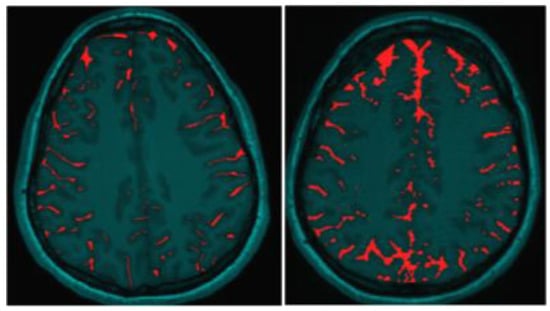

The most readily observed changes were increases in the width of the sulci in many of the players, as illustrated in Figure 1. The most profound changes appeared in the athletes who had experienced concussive events but the sulci were also widened in the soccer players who did not have reported concussions. Because we observed increases in width of the sulci in players, the changes in brain volume of each individual athlete were calculated to quantify the changes as described in the Methods section. The changes in the calculated longitudinal relative total brain volume of seven athletes over the years is shown in Figure 2. In addition to the widening of the sulci in the frontal, parietal, and occipital regions of the brain, we observed low-intensity punctate regions in the white matter interfaces on T2- and susceptibility-weighted images associated with the base of the sulci (Figure 3). Four of the players imaged over four years exhibited reductions in brain volume (Athletes 10, 11, 12, 15) while the remaining athletes exhibited no change in relative brain volume over the multiyear period. Only one of the players with reduced brain volume, Athlete 15, sustained a concussive event while the other three did not have reported concussions. She had a concussion during her first year at the University. An additional athlete (Player 29) was evaluated using MRI (Figure 4, pre- and post-concussion) and the IMPACT tool following the concussion and then again four days later. The MRI revealed increases in the sulcal volume in the region of the pre- to post-central sulci following the concussive event. Athlete 29 was not imaged for four consecutive years and so was not included in Figure 2. From these observations, it appears that overt concussive events are not required for there to be a reduction in brain volume. The reduction of two percent in the longitudinal relative brain volume of the four athletes is unusual when compared with the metadata analysis reported in Hedman et al. []. The brain volume in normal women between the ages of 18 and 25 generally increases two to three percent or remains the same during this developmental stage; this is the age range of athletes in our study.

Figure 1.

Illustration of increased Sulcal Volume in the brain of Women Soccer players before (left image) and after (right image) concussive events. The red coloring indicates the Sulcal volume.